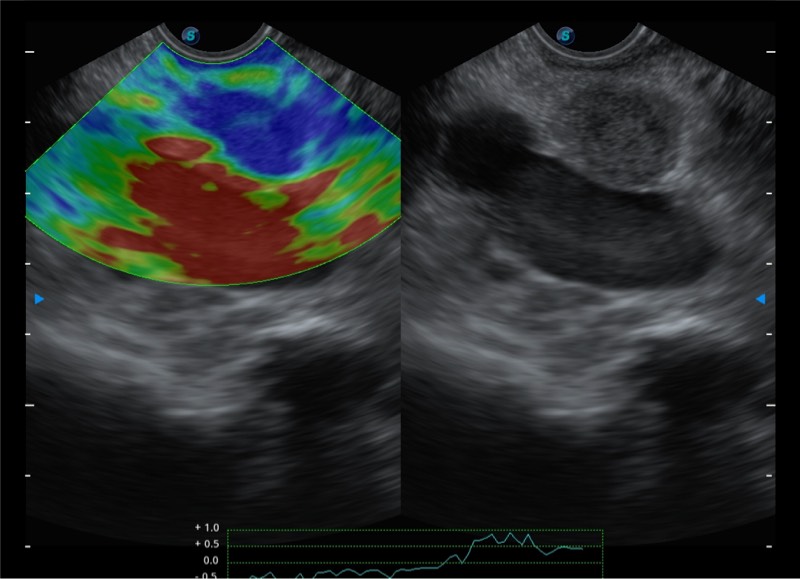

基于二十年的超声技术积累,狗万官方网站提供了最新一代的独立超声主机,在提供高质量图像的同时满足多学科使用。具备常见多普勒技术并提供弹性成像、声学造影等高端影像技术。新一代传感器具有更强的抗干扰能力并减少图像伪影。

4-12MHZ宽频输出